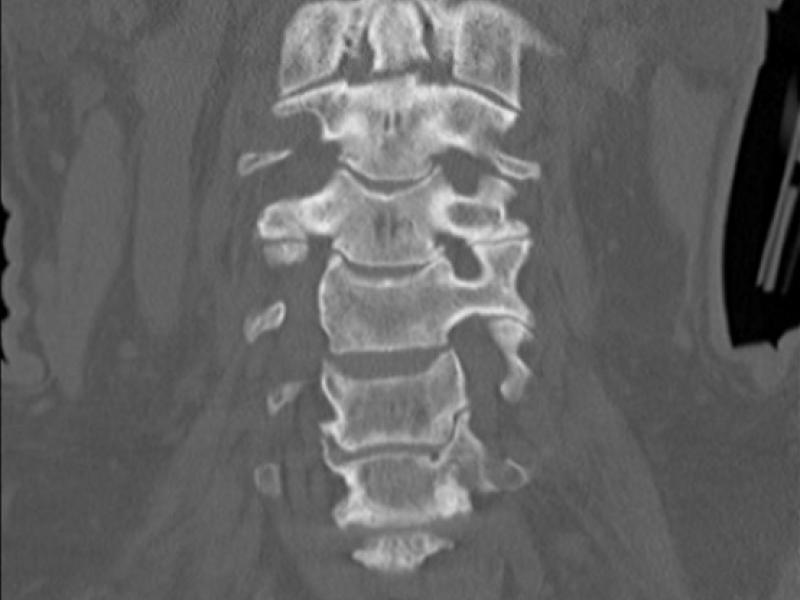

What's the diagnosis?  By Dr. Eric Chavis

October 07 2020

A70 yo male presents after MVC. He remembers waking up at